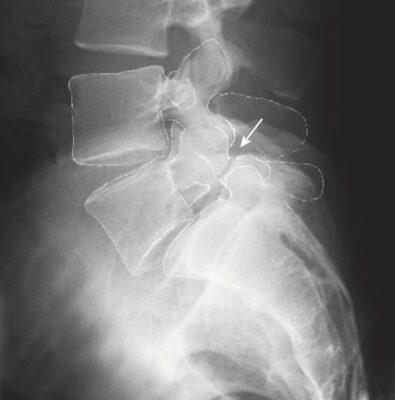

- Trước đây, xét nghiệm tiêu chuẩn để đánh giá một trẻ nghi ngờ bị hở eo là chụp X quang cột sống thắt lưng thẳng, nghiêng, chếch trái và chếch phải. Phim nghiêng phát hiện và đánh giá mức độ trượt đốt sống. Phim chếch có thể cho thấy dấu hiệu “vòng cổ của chú chó Scottie” cổ điển của hở eo. Độ nhạy của phim chếch chỉ đạt tới 33%, và các nghiên cứu gần đây cho thấy các phim chếch ít có giá trị bổ sung cho phim thẳng và nghiêng thông thường.

- Phân độ trượt đốt sống trên X quang: Mức độ trượt đốt sống ra trước được xác định bằng tỷ lệ phần trăm trượt của góc sau – dưới của thân đốt sống ở trên so với mặt trên của thân đốt sống bên dưới (Phân độ Meyer). Trượt ít nhất 5% mới chẩn đoán xác định là có trượt đốt sống.

- Độ I: trượt từ 5% đến 25%;

- Độ II – 26% đến 50%;

- Độ III – 51% đến 75%;

- Độ IV – hơn 75%; và

- Độ V là trật hoàn toàn so với đốt sống lân cận, còn được gọi là sa đốt sống (spondyloptosis).

- Hầu hết các trường hợp (60% đến 75%) là ở độ I; 20% đến 38% ở độ II; và dưới 2% trường hợp trượt đốt sống là ở độ III, IV và V.